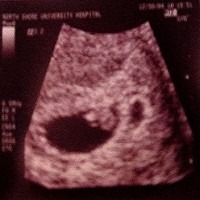

Bij het 'Verdwijnende Tweeling Syndroom' (VTS) is er sprake van een tweelingzwangerschap. In een vroeg stadium stopt echter een van de twee vruchtjes met groeien.

Soms merk je daar niets van. Omdat tegenwoordig in een vroeg stadium echo's worden gemaakt, zijn steeds meer vrouwen zich bewust van het feit dat ze zwanger waren van een tweeling.

Doordat het levende kindje doorgroeit, wordt het vruchtzakje van het andere kindje steeds meer verdrukt en minder zichtbaar.